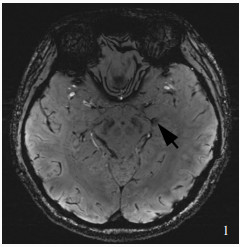

Hageman G , Hof J , Nihom J . Susceptibility-weighted MRI and microbleeds in mild traumatic brain injury: prediction of posttraumatic complaints?. Eur Neurol, 2022, 85: 177- 185.

| 24 |